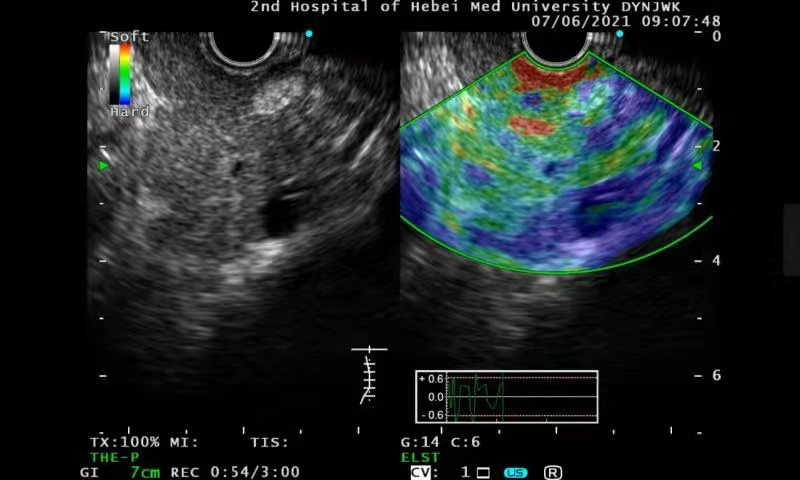

弹性成像